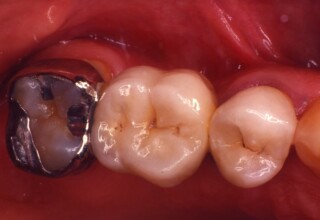

Fixed Restoration combining a classical and a resin-bonded retainer (RBR)

A missing upper premolar was replaced by a fixed bridge. The anterior abutment was previously restored with a crown, so a classic full coverage crown served as the anterior bridge retainer. The posterior abutment was an unprepared, unfilled tooth with an extensive gingival recession. In order to avoid extensive preparation and a concomitant root canal, a partial metal retainer (a 360o Maryland type wing) was used. It provides adequate retention since 2008.